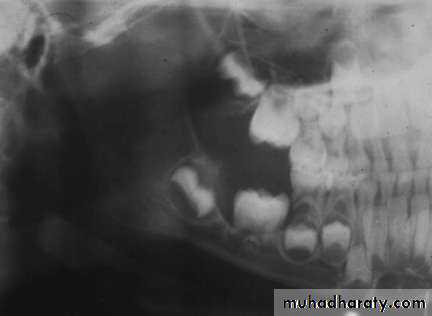

• Radiography:• Uni or Multilocular radiolucent areas

• Soap bubbles

• Copyright 2003, Elsevier Science (USA). All rights reserved.• Ameloblastoma

• Radiography:

• Soap bubbles appearance